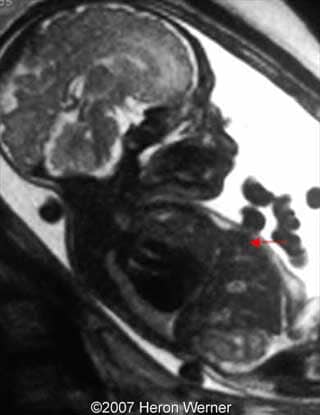

Figure 13: Sagittal T2-weighted MR image shows the left diaphragmatic hernia. Note the intestinal loops inside left side of the thorax (arrow).

Figures 10, 11, 12: Sagittal T2-weighted shows the liver-up (blue arrow) and the stomach in the chest (red arrow).